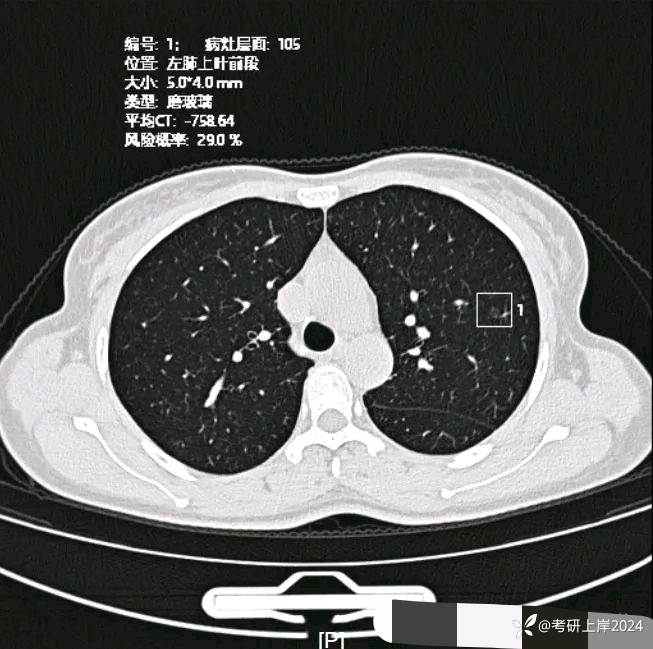

患者最近的检查有AI辅助诊断意见,找出的病灶分别如下:

病灶10:左上叶极淡密度的小片状模糊影,少许纤维增生或肺泡上皮增生;

病灶12:左上叶磨玻璃结节,轮廓较清,有血管穿行,考虑肺泡上皮不典型增生可能性较大,也可能原位癌;

病灶15:左上叶微小磨玻璃结节,轮廓较清,紧贴叶间裂,考虑肺泡上皮增生可能性较大;

病灶17:左上叶磨玻璃结节,伴小空泡征,也有微血管征,考虑原位癌可能性较大。